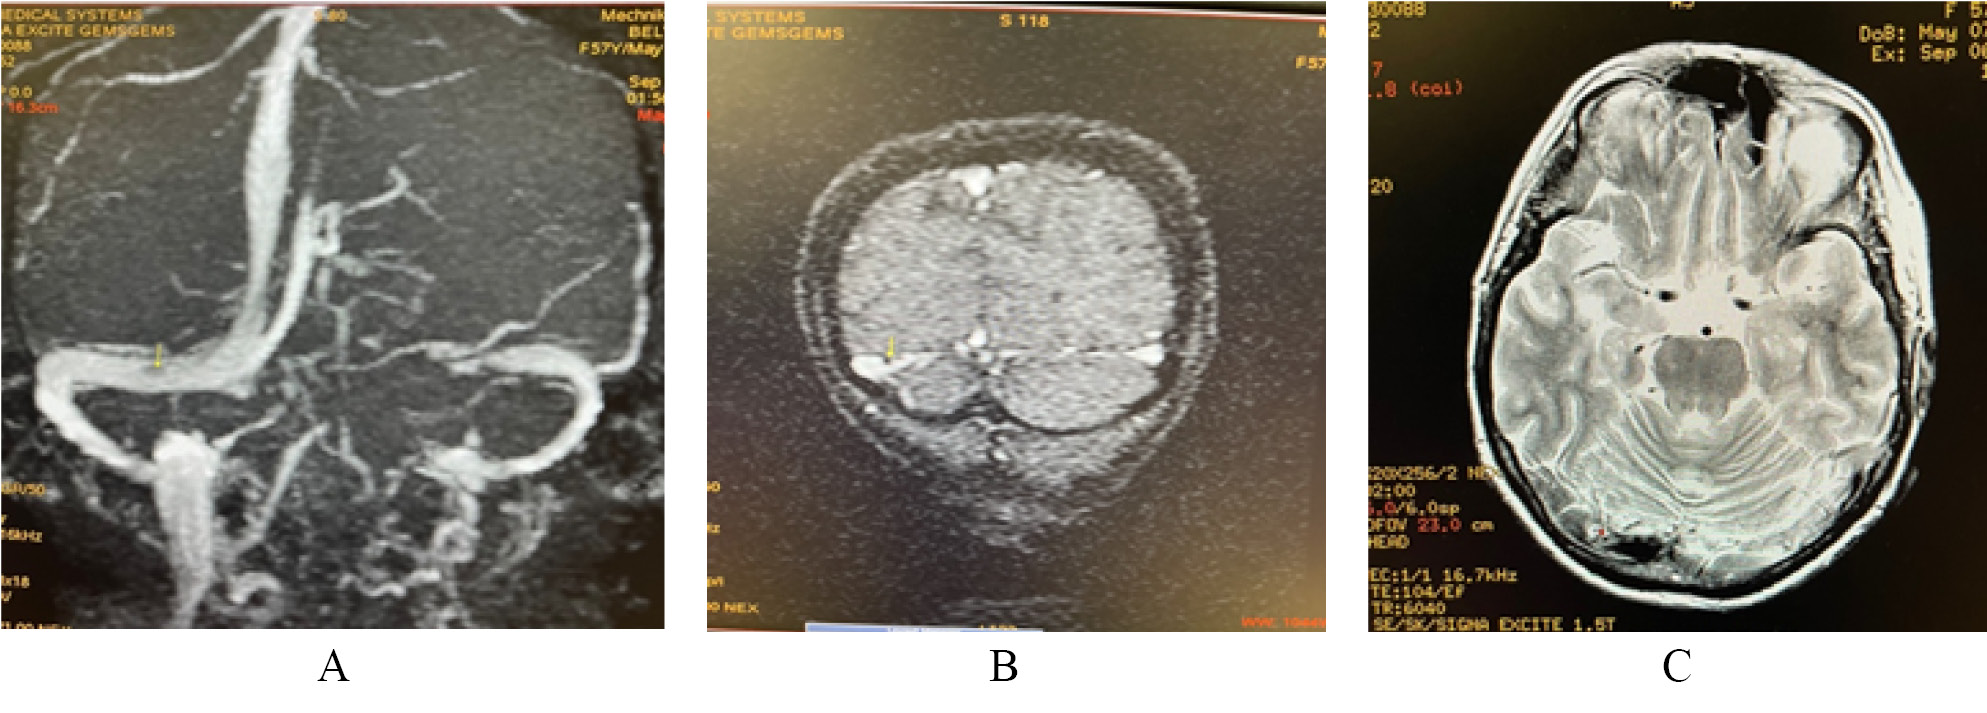

МРТ головного мозга с внутривенным контрастированием от 23.03.2021. Субкортикально и паравентрикулярно в белом веществе головного мозга в височных, лобных и теменных долях (от 4 до 8 мм), в левой лобной доле (16×14 мм), в правой височной доле (до 20×13 мм), в области базальных ядер (до 3 мм) визуализируются множественные очаги глиоза с нечёткими контурами, склонные к слиянию, характеризующиеся гиперинтенсивным сигналом на Т2-взвешенных изображениях (ВИ), изоинтенсивным на Т1-ВИ, без перифокального отёка и масс-эффекта. Очаги не имеют признаков ограничения и магнитно-резонансной (МР) диффузии, не накапливают контрастное вещество (рис. 2).

Рис. 2. Очаги гиперинтенсивного магнитно-резоненсного сигнала на Т2-взвешенном изображении и импульсная последовательность FLAIR в правой височной доле (Б); в белом веществе лобных долей

Заключение. МР-картина множественных очаговых изменений головного мозга дистрофического и дисциркуляторного характера, без признаков ограничения МР-диффузии и накопления контрастного вещества. Умеренная наружная заместительная гидроцефалия. Учитывая относительно молодой возраст пациентки и выраженные изменения белого вещества головного мозга, помимо ранних морфологических проявлений дисциркуляторной энцефалопатии, необходимо исключить наличие генетически детерминированной артериолопатии по типу ЦАДАСИЛ (поражение височных долей, ранний клинический признак — мигрень, снижение памяти). Демиелинизирующий процесс вне стадии активности — наименее вероятен (очаги в области мозолистого тела отсутствуют).